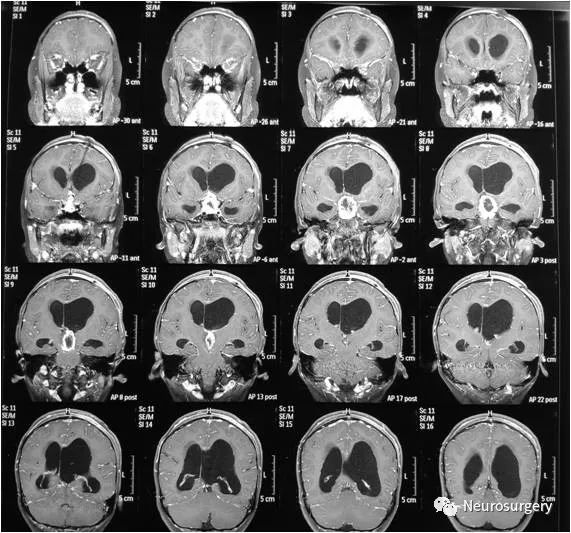

女性,11岁,间断头痛、恶心1年,双眼模糊1月,加重1周。PE:双眼视力下降,余无明显异常。既往体健。头MRI:鞍内、鞍上、三脑室、下丘脑占位,伴幕上脑积水。

术式:冠切右额开颅肿瘤切除术,术中见肿瘤位于鞍内、鞍上、三脑室及下丘脑,呈灰红色,质地中等,血供极为丰富,边界不清,给予镜下切除,术中出血约2500ml,输入异体红细胞2400ml,血浆1000ml。

术后当天查双侧瞳孔不等大,左:右为2.0mm:2.5mm。急查头颅CT示左额硬膜外血肿,双侧侧脑室及四脑室可见血性高密度影。

急诊行冠切左额开颅硬膜外血肿清除术,术中清除血肿约80ml,手术过程顺利,术中出血约50ml,未输血。

术后恢复良好,顺利出院。病理:毛细胞型星形细胞瘤(WHO-I级)